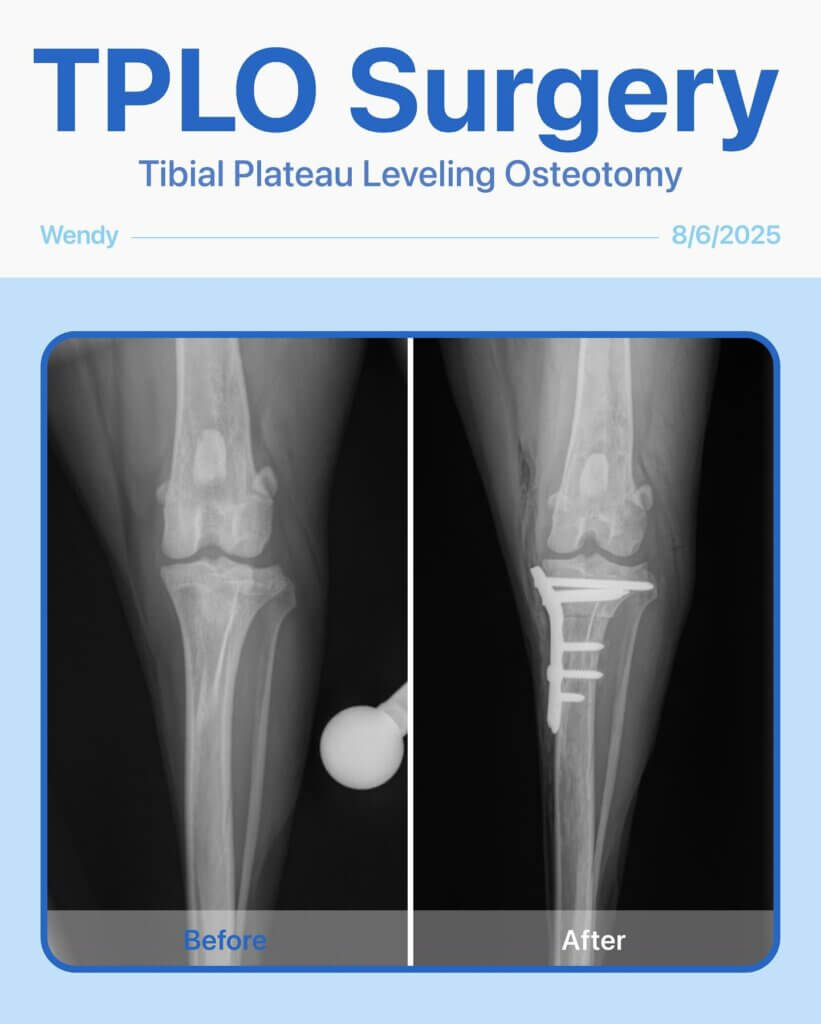

Stronger Than Ever: Wendy’s Story. Last year, Wendy, our brave 7-year-old English Shepherd, had a TPLO surgery on her back left leg. Recently, her back right leg started limping, and after a careful exam, we found that she needed another TPLO surgery.

The surgery went smoothly, and Wendy is now on the road to recovery, already showing her resilience and happy spirit. We’re so proud of her!